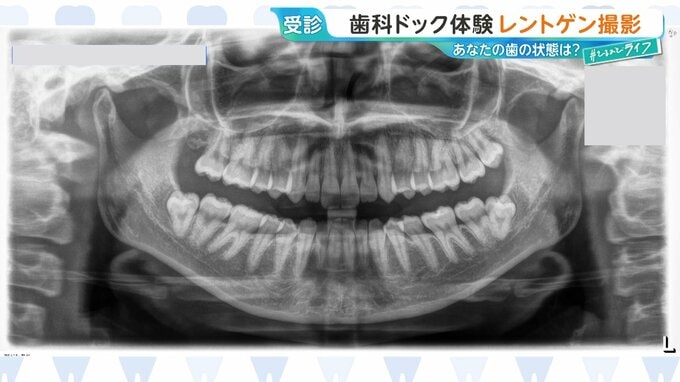

〈3〉レントゲン撮影

撮影は約1分で終了。

虫歯や歯周病の状況を確認し、歯科医師がアドバイスをします。

レントゲン写真などを参考にレーザーの光をあてて確認します。